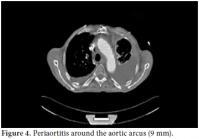

A 61-year-old male patient was admitted to our outpatient unit with dyspnea, edema on the legs, and chest pain. The physical examination was unremarkable except for exophthalmos, tachypnea, S3 edema, and bilateral pretibial pitting edema, and the laboratory investigation revealed the following levels: blood urea nitrogen 94 mg/dL, creatinin 1.38 mg/dL, and C-reactive protein (CRP) 1.53 mg/dl. The anti nuclear antibody (ANA) revealed a negative result. The globulin levels were within normal limits; therefore, IgG and E levels were not analyzed. The patient had no history of autoimmune or allergic diseases. An echocardiographic evaluation was performed to rule out heart failure and massive pericardial effusion, and a mass at the right atrial wall was detected. Nearly 1500 cc pericardial fluid was aspirated by pericardiosynthesis for the relief of the dyspnea. The examinations for tuberculosis revealed negative results, but atypical mesothelial and inflammatory cells were seen in the cytological evaluation. Therefore, computed tomography (CT) of the abdomen and thorax was ordered for further evaluation and pericardial effusion and periaortitis was detected beginning from the arcus and lasting to the abdominal aorta (Figures 1 and 2). On the cardiac CT scan, three soft tissues arising from the right coronary artery and extending to the right atrium were seen (Figure 3). The serologic tests for perinuclear anti-neutrophil cytoplasmic antibodies (p-ANCA) and cytoplasmic anti-neutrophil cytoplasmic autoantibody (c-ANCA) were negative. The radiological evaluation of the exophthalmos with cranial CT revealed bilateral retro-orbital pseudotumors, although the thyroidstimulating hormone level was normal (Figure 4). By all of these radiological findings, IgG4-related sclerosing vasculitis was first suspected, and the level of IgG4 was found to be 148 (0-125) U/ml. The patient was referred to the cardiovascular surgeons for a biopsy from the mass in the right atrium. The histological evaluation of the biopsy material revealed lymphoplasmacytic infiltration fibrosis, a lymphoid follicle, and eosinophilic infiltration. These findings were concordant with IgG4-related sclerosing vasculitis. The arterial constrictions in the right coronary artery and circumflex artery were removed by percutaneous balloon angioplasty and two cardiac stents a cardiac pacemaker were implanted.